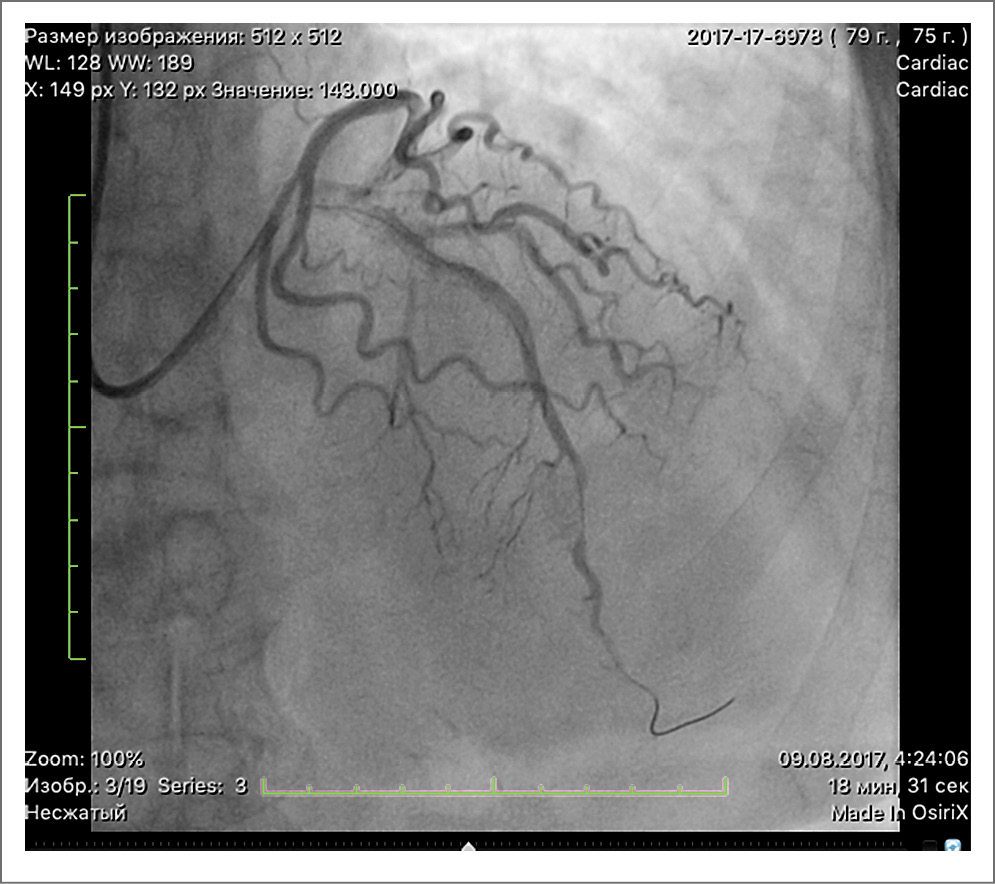

Учитывая наличие факторов риска, сохраняющиеся приступы стенокардии при минимальной физической нагрузке, на фоне оптимальной медикаментозной терапии, пациентке решено выполнить коронароангиографию (КАГ). При проведении исследования выявлено, что у пациентки сбалансированный тип кровоснабжения, а также многососудистое поражение крупных коронарных артерий. Передняя нисходящая артерия (ПНА) в проксимальном сегменте стенозирована на 90%, диагональная артерия (ДА) в устье стенозирована на 70%, огибающая артерия в проксимальной трети – на 30%. Правая коронарная артерия с неровными контурами. На рис. 1 представлено поражение ПНА в проксимальном сегменте, ДА, стенозированной в устье на 70%. Принято решение о проведении эндоваскулярного лечения: транслюминальной баллонной ангиопластики передней нисходящей артерии и ДА со стентированием.

Рис. 1. Поражение ПНА в проксимальном сегменте, ДА, стенозированной в устье на 70%